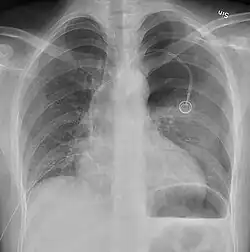

Chest X-ray

A plain chest radiograph, ideally with the X-ray beams being projected from the back (posteroanterior, or "PA"), and during maximal inspiration (holding one's breath), is the most appropriate first investigation.[35] It is not believed that routinely taking images during expiration would confer any benefit.[36] Still, they may be useful in the detection of a pneumothorax when clinical suspicion is high but yet an inspiratory radiograph appears normal.[37] Also, if the PA X-ray does not show a pneumothorax but there is a strong suspicion of one, lateral X-rays (with beams projecting from the side) may be performed, but this is not routine practice.[18][22]

-

Anteroposterior inspired X-ray, showing subtle left-sided pneumothorax caused by port insertion -

Lateral inspired X-ray at the same time, more clearly showing the pneumothorax posteriorly in this case -

Anteroposterior expired X-ray at the same time, more clearly showing the pneumothorax in this case -

Chest X-ray showing a pneumothorax on the right (left in the image), where the absence of lung markings indicates that there is free air inside the chest -

Chest X-ray showing the features of pneumothorax on the left side of the person (right in image)

It is not unusual for the mediastinum (the structure between the lungs that contains the heart, great blood vessels, and large airways) to be shifted away from the affected lung due to the pressure differences. This is not equivalent to a tension pneumothorax, which is determined mainly by the constellation of symptoms, hypoxia, and shock.[16]

The size of the pneumothorax (i.e. the volume of air in the pleural space) can be determined with a reasonable degree of accuracy by measuring the distance between the chest wall and the lung. This is relevant to treatment, as smaller pneumothoraces may be managed differently. An air rim of 2 cm means that the pneumothorax occupies about 50% of the hemithorax.[18] British professional guidelines have traditionally stated that the measurement should be performed at the level of the hilum (where blood vessels and airways enter the lung) with 2 cm as the cutoff,[18] while American guidelines state that the measurement should be done at the apex (top) of the lung with 3 cm differentiating between a "small" and a "large" pneumothorax.[38] The latter method may overestimate the size of a pneumothorax if it is located mainly at the apex, which is a common occurrence.[18] The various methods correlate poorly but are the best easily available ways of estimating pneumothorax size.[18][22] CT scanning (see below) can provide a more accurate determination of the size of the pneumothorax, but its routine use in this setting is not recommended.[38]

Not all pneumothoraces are uniform; some only form a pocket of air in a particular place in the chest.[18] Small amounts of fluid may be noted on the chest X-ray (hydropneumothorax); this may be blood (hemopneumothorax).[16] In some cases, the only significant abnormality may be the "deep sulcus sign", in which the normally small space between the chest wall and the diaphragm appears enlarged due to the abnormal presence of fluid.[19]